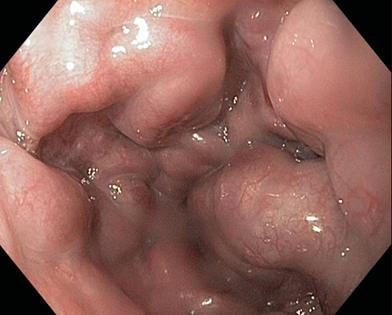

Hình ảnh giãn tĩnh mạch thực quản độ II-III